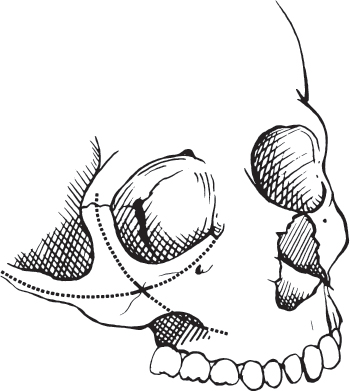

The zygoma is a relatively sturdy bone that provides the aesthetically important malar eminence. It joins the surrounding craniofacial skeleton through four superficial and two deep projections. Superficially, the projections contribute to two critical external arcs of contour ( Fig. 62.1 ). The vertical arc runs from the zygomatic process of the frontal bone over the zygoma to the zygomaticomaxillary (ZM) buttress area of the lateral wall of the maxillary antrum above the first molar. The longer horizontal arc runs from the maxilla in the area of the lacrimal fossa around the zygoma to the root of the zygomatic process of the temporal bone. It is parallel to, but slightly below, the Frankfort horizontal plane. Because the height of contour of the malar eminence is also just at or slightly inferior to the Frankfort plane, the point of intersection of these arcs of contour defines the position of the malar eminence, typically 2 cm inferior to the lateral canthus ( Fig. 62.1 ). The two deep projections are the sphenoid projection that articulates along the lateral orbital wall with the orbital plate of the sphenoid bone and the orbital projection that articulates with the orbital surface of the maxilla in the extreme lateral aspect of the orbital floor. The sphenoid and orbital projections lie beneath and perpendicular to the external arcs of contour in the area of the inferolateral orbital rim, thus greatly strengthening this portion of the rim.

The zygomatic arch typically either fractures near its midpoint in a single location or in two places resulting in a central fragment susceptible to displacement and rotation. Therefore, fracture dislocations of the zygoma may fragment both ends of the horizontal arc of contour and the lower end of the vertical arc. The degree of this disruption and the amount of displacement of the zygoma determine the severity of the injury and thus the complexity of the needed repair. Reconstruction of the horizontal arc restores anterior and lateral projection of the cheek, and reconstruction of the vertical arc restores the height of the malar eminence in relation to the Frankfort plane.